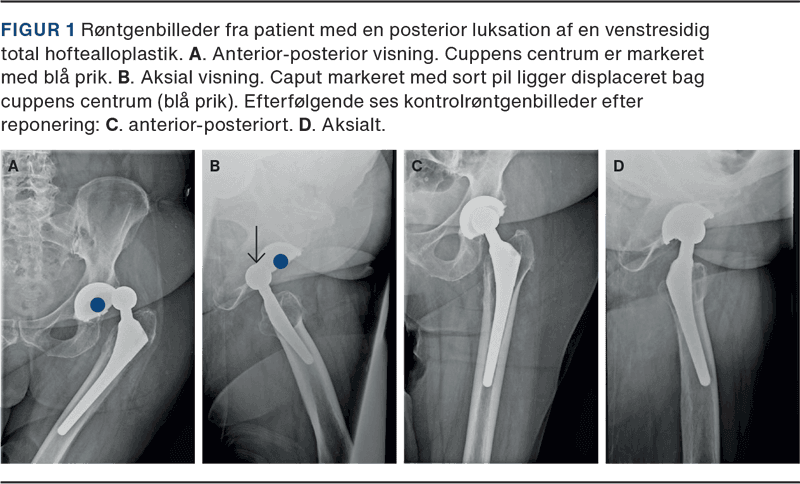

THA-luksation defineres som komplet displacering af metalhovedet, dvs. caput, fra acetabularkomponenten, dvs. cuppen. Den typiske luksation opstår i forbindelse med hurtige bevægelser med en for kraftig fleksion i hoften, evt. kombineret med indadrotation. Det resulterer i en posterior luksation (Figur 1), hvorimod strækning af hoften og samtidig udadrotation kan føre til anterior luksation. Klassiske mekanismer herfor omfatter mobilisering fra en lav stol eller seng, fremadbøjning for at tage strømper på eller binde sko eller ved et faldtraume [10]. Luksationen medfører øjeblikkelig intens smerte og manglende evne til mobilisering. Klinisk set er man sjældent i tvivl om diagnosen, og der er fejlstilling og forkortning af benet (flekteret, indadroteret hofte ved posterior luksation; ekstenderet, udadroteret hofte ved anterior luksation). Røntgenundersøgelse er nødvendig for at bekræfte diagnosen og for at udelukke periprostetisk fraktur. Langt størstedelen af luksationerne kan behandles med lukket reponering under enten sedation eller en kort general anæstesi. Akut åben kirurgi er sjældent nødvendig [11].